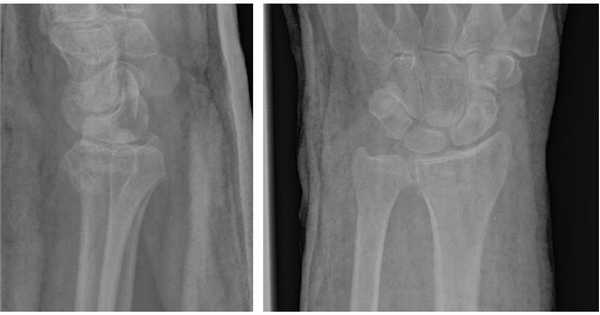

Рис. 1. Внутрисуставной нестабильный перелом лучевой кости.

Рис. 2. . тот же перелом после закрытой репозиции (полного сопоставления отломков нет).

На представленной рентгенограмме не тренированный глаз может вообще не увидеть перелома, хотя врач травматолог и квалифицированный рентгенолог заметят насколько «просела» суставная поверхность лучевой кости, и отметят, что она развёрнута в тыльную сторону на 10 градусов (в норме она должна смотреть в ладонную сторону). Если присмотреться повнимательнее становятся видны линии перелома.